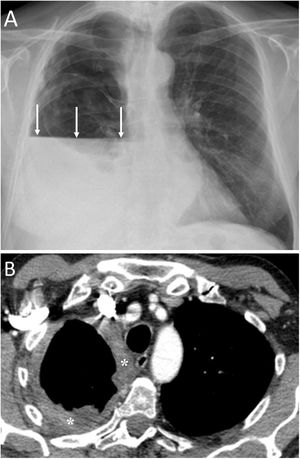

Bilateral spontaneous PTX, which represents 1.3% of spontaneous PTX, has also been described as a complication of a unilateral transthoracic puncture29 (Fig. 12).

A 72-year-old man with a pulmonary nodule in the right upper lobe. Percutaneous fine needle (22 G) lung puncture cytology was of a non-small cell lung neoplasm. A and B) The chest X-ray 72 h after the procedure revealed signs of pneumomediastinum and significant subcutaneous emphysema (white arrows). The biopsied pulmonary nodule can be seen in the periphery of the right upper lobe in the posteroanterior view of the chest X-ray (black arrows). B and C) Computed tomography confirmed pneumomediastinum and subcutaneous emphysema and showed predominantly left bilateral pneumothorax (white arrows) with communication between both pleural spaces in the anterior junctional line (black arrows), probably of congenital origin, since there was no previous thoracic surgery. The subcutaneous emphysema was drained through an incision in the chest wall and multiple pleural adhesions were identified during the surgical procedure of right upper lobectomy.

It must be remembered that: exceptionally, there is communication between the two pleural spaces in the anterior junctional line, which results in a single pleural space. This may be secondary to previous surgery with median sternotomy ("iatrogenic buffalo chest'') or a communication of congenital origin.29,30

Communication between the two pleural spaces after heart and lung transplantation has been observed in 33%–40% of these patients, which can lead to bilateral PTX.30 CT can identify communication between the two pleural spaces. Treatment will usually consist of unilateral pleural drainage.30